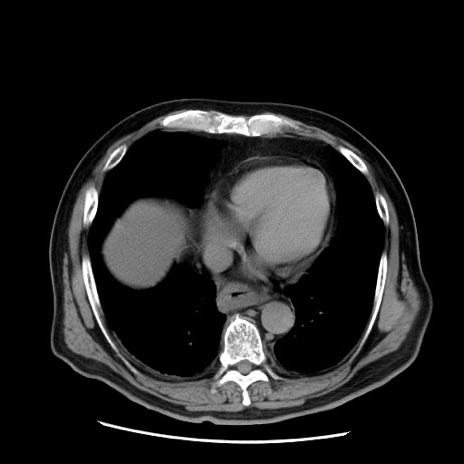

症例20(横断像)

【症例】 60歳代男性

【主訴】 腹部膨満、嘔吐

【現病歴】5日前頃より倦怠感を認め食事量減少し4日前の朝嘔吐、食事摂取困難となった。 3日前近医受診し点滴施行され整腸剤などを処方された。 当日他院を受診し、腹部膨満著明、炎症反応の上昇(CRP10.8、WBC11200)あり、紹介受診となる。

【身体所見】 意識JCS1 受け答えがはっきりしないBP 111/57mHg、 P 67bpm、、BT35.2°C、SpO2 97%(RA)、 腹部:膨隆、打診で鼓音あり、全体的に圧痛有り、腸蠕動音(-)、反跳痛ははっきりせず。

【データ】WBC 11400、CRP 14.20